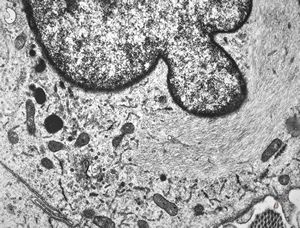

M, 70y. | mycosis fungoides - Sézary cell